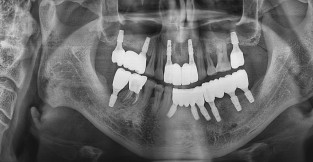

• 2

전체 임플란트

치료기간 : 2024-08-13 ~ 2025-01-03

1. 상기 x-ray 이미지 모두 동일한 해당 의료기관에서 진료한 환자입니다.

2. 상기 x-ray 이미지 모두 동일 인물의 것입니다.

3. 치료 전 이미지는 2024-08-13에 촬영했으며, 치료 후 이미지는 2025-01-03에 촬영하였습니다.

4. 상기 x-ray 이미지 모두 동일 조건에서 환자분의 동의를 받아촬영되었습니다.

* 임플란트 시술은 환자분의 상태(고혈압, 당뇨 등)에 따라 부작용이 있을 수 있으니, 반드시 전문의와 상담이 필요합니다.

* 임플란트 수술 부작용

: 수술 후 출혈, 교합, 통증, 붓기, 염증 등의 문제점이 발생할 수 있습니다.)